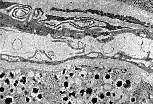

Dans cet acinus pancréatique observé au M.E.T., une cellule centro-acineuse est particulièrement bien visible. Son cytoplasme clair contraste avec celui des cellules séreuses encombré de grains de zymogène.

En M.E.T., il est aisé de distinguer les cellules endocrines des cellules séreuses pancréatiques.

Les cellules séreuses se reconnaissent à leurs grains de zymogène et leur disposition en acinus.

Les cellules endocrines regroupées en cordons au sein des îlots présentent un cytoplasme plus clair et un noyau central.

Chaque variété de cellule endocrine du pancréas possède des grains de sécrétion caractéristiques qui permettent son identification au M.E.T. Ainsi, les cellules ß sécrétant l'insuline ont des grains contenant une formation dense souvent géométrique entouré d'un espace clair.